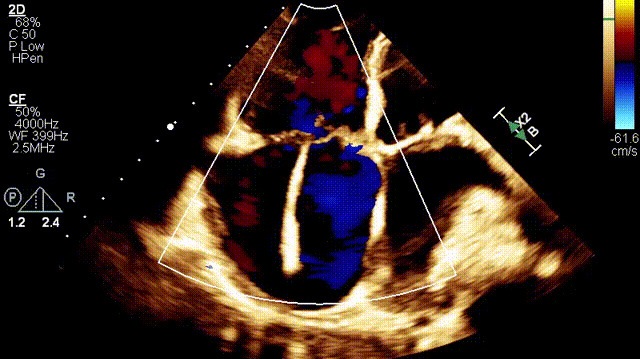

植入前超聲

接受治療的是一例89歲的超高齡女性患者,主訴“起搏器術(shù)后7年余,反復(fù)氣促4年”,因反復(fù)心衰失代償,胸腔積液就診。術(shù)前超聲提示:1.雙房及右室擴大(右室舒張末和收縮末容積分別為55ml和21ml,右室FAC27%);2.三尖瓣瓣環(huán)擴張(瓣環(huán)左右徑41mm,前葉長度21.3mm,隔葉長度15.2mm,后葉長度23.1mm),瓣葉閉合不攏;3.功能性重度三尖瓣反流(FTR 5+,收縮期三尖瓣口反流束縮流頸寬度21mm);4.下腔靜脈內(nèi)徑約25mm,呼吸塌陷率<50%;5.輕度肺高壓。術(shù)前CT結(jié)果顯示,入路血管最小平均徑約9.6mm,入路血管無嚴(yán)重迂曲、鈣化。隨后,王焱教授及其團隊王斌教授、陳翔教授、超聲科蘇茂龍主任、手術(shù)室溫紅梅護士長進行了詳細而周密的術(shù)前討論,最終選擇我國自主研發(fā)的LuX-Valve Plus經(jīng)血管三尖瓣置換系統(tǒng)對患者進行手術(shù)。